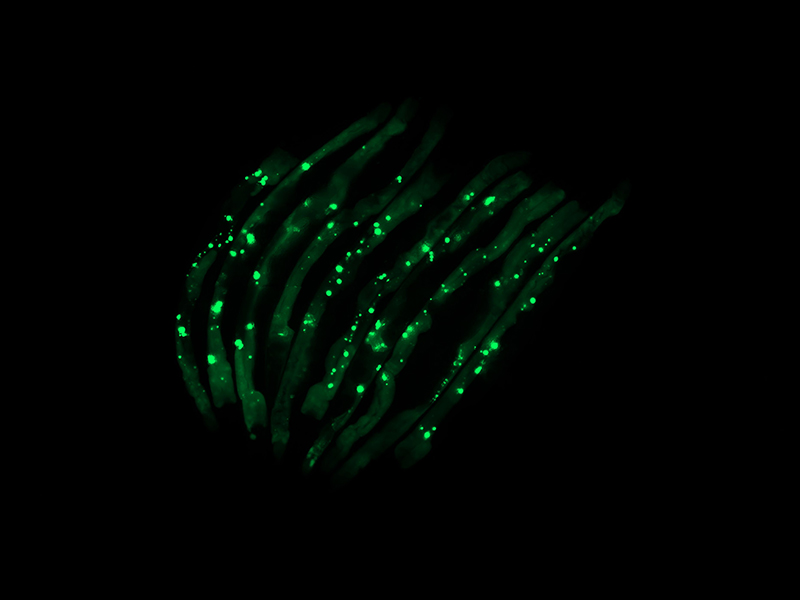

“That is, in fact, what we observed. We have a way of marking the aggregates so they glow green under the microscope. We saw that worms colonized by certain bacteria species were lit up with aggregates that were toxic to tissues, while those colonized by the control bacteria were not,” Czyz said. “This occurred not just in the intestinal tissues, where the bacteria are, but all over the worms’ bodies, in their muscles, nerves and even reproductive organs.”